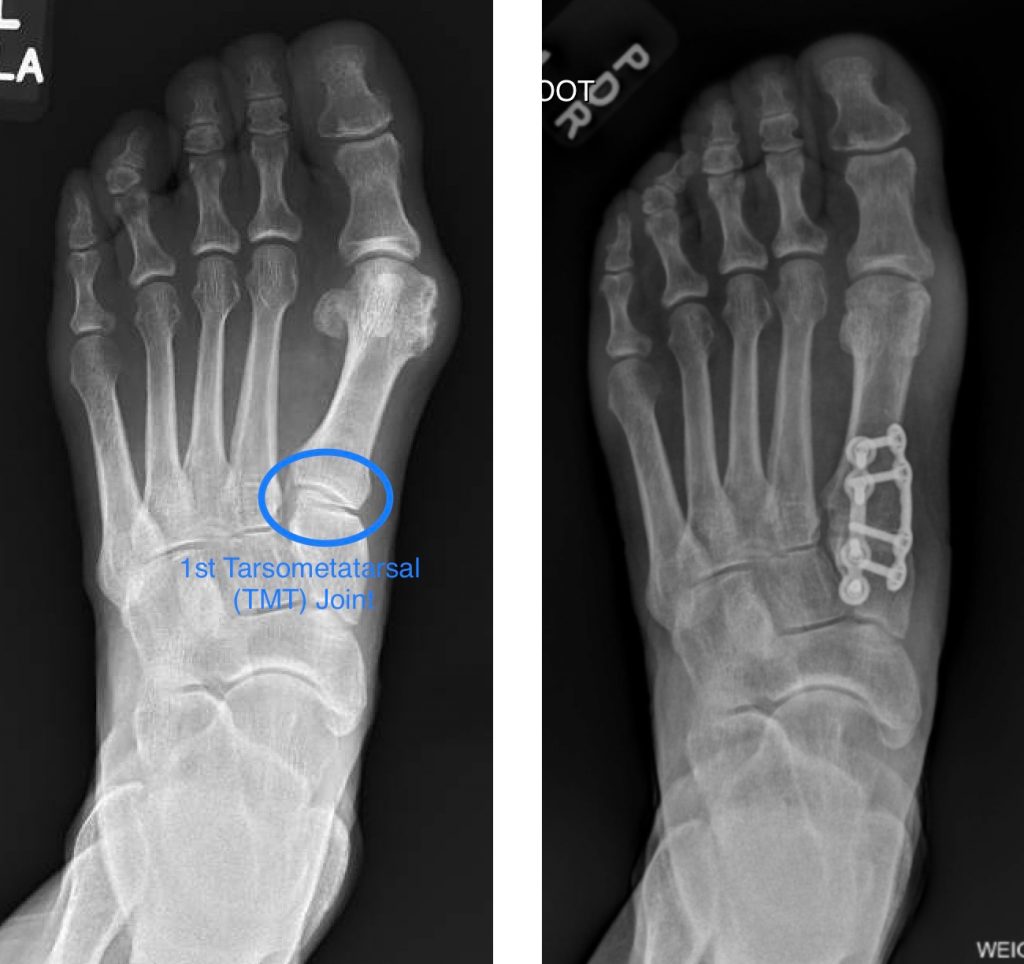

Bunion Correction Alpine Foot Specialists Foot Bunion Specialist Lapiplasty is an innovative solution for bunions, surgically correcting and securing the alignment of your bones to repair your foot. Bunion correction treatment is provided by our expert podiatrists at ohio foot & ankle specialists, using minimally invasive procedures for quick recovery and less pain. Schedule an appointment online or by phone today to find out how the. If you’re. Foot Bunion Specialist.